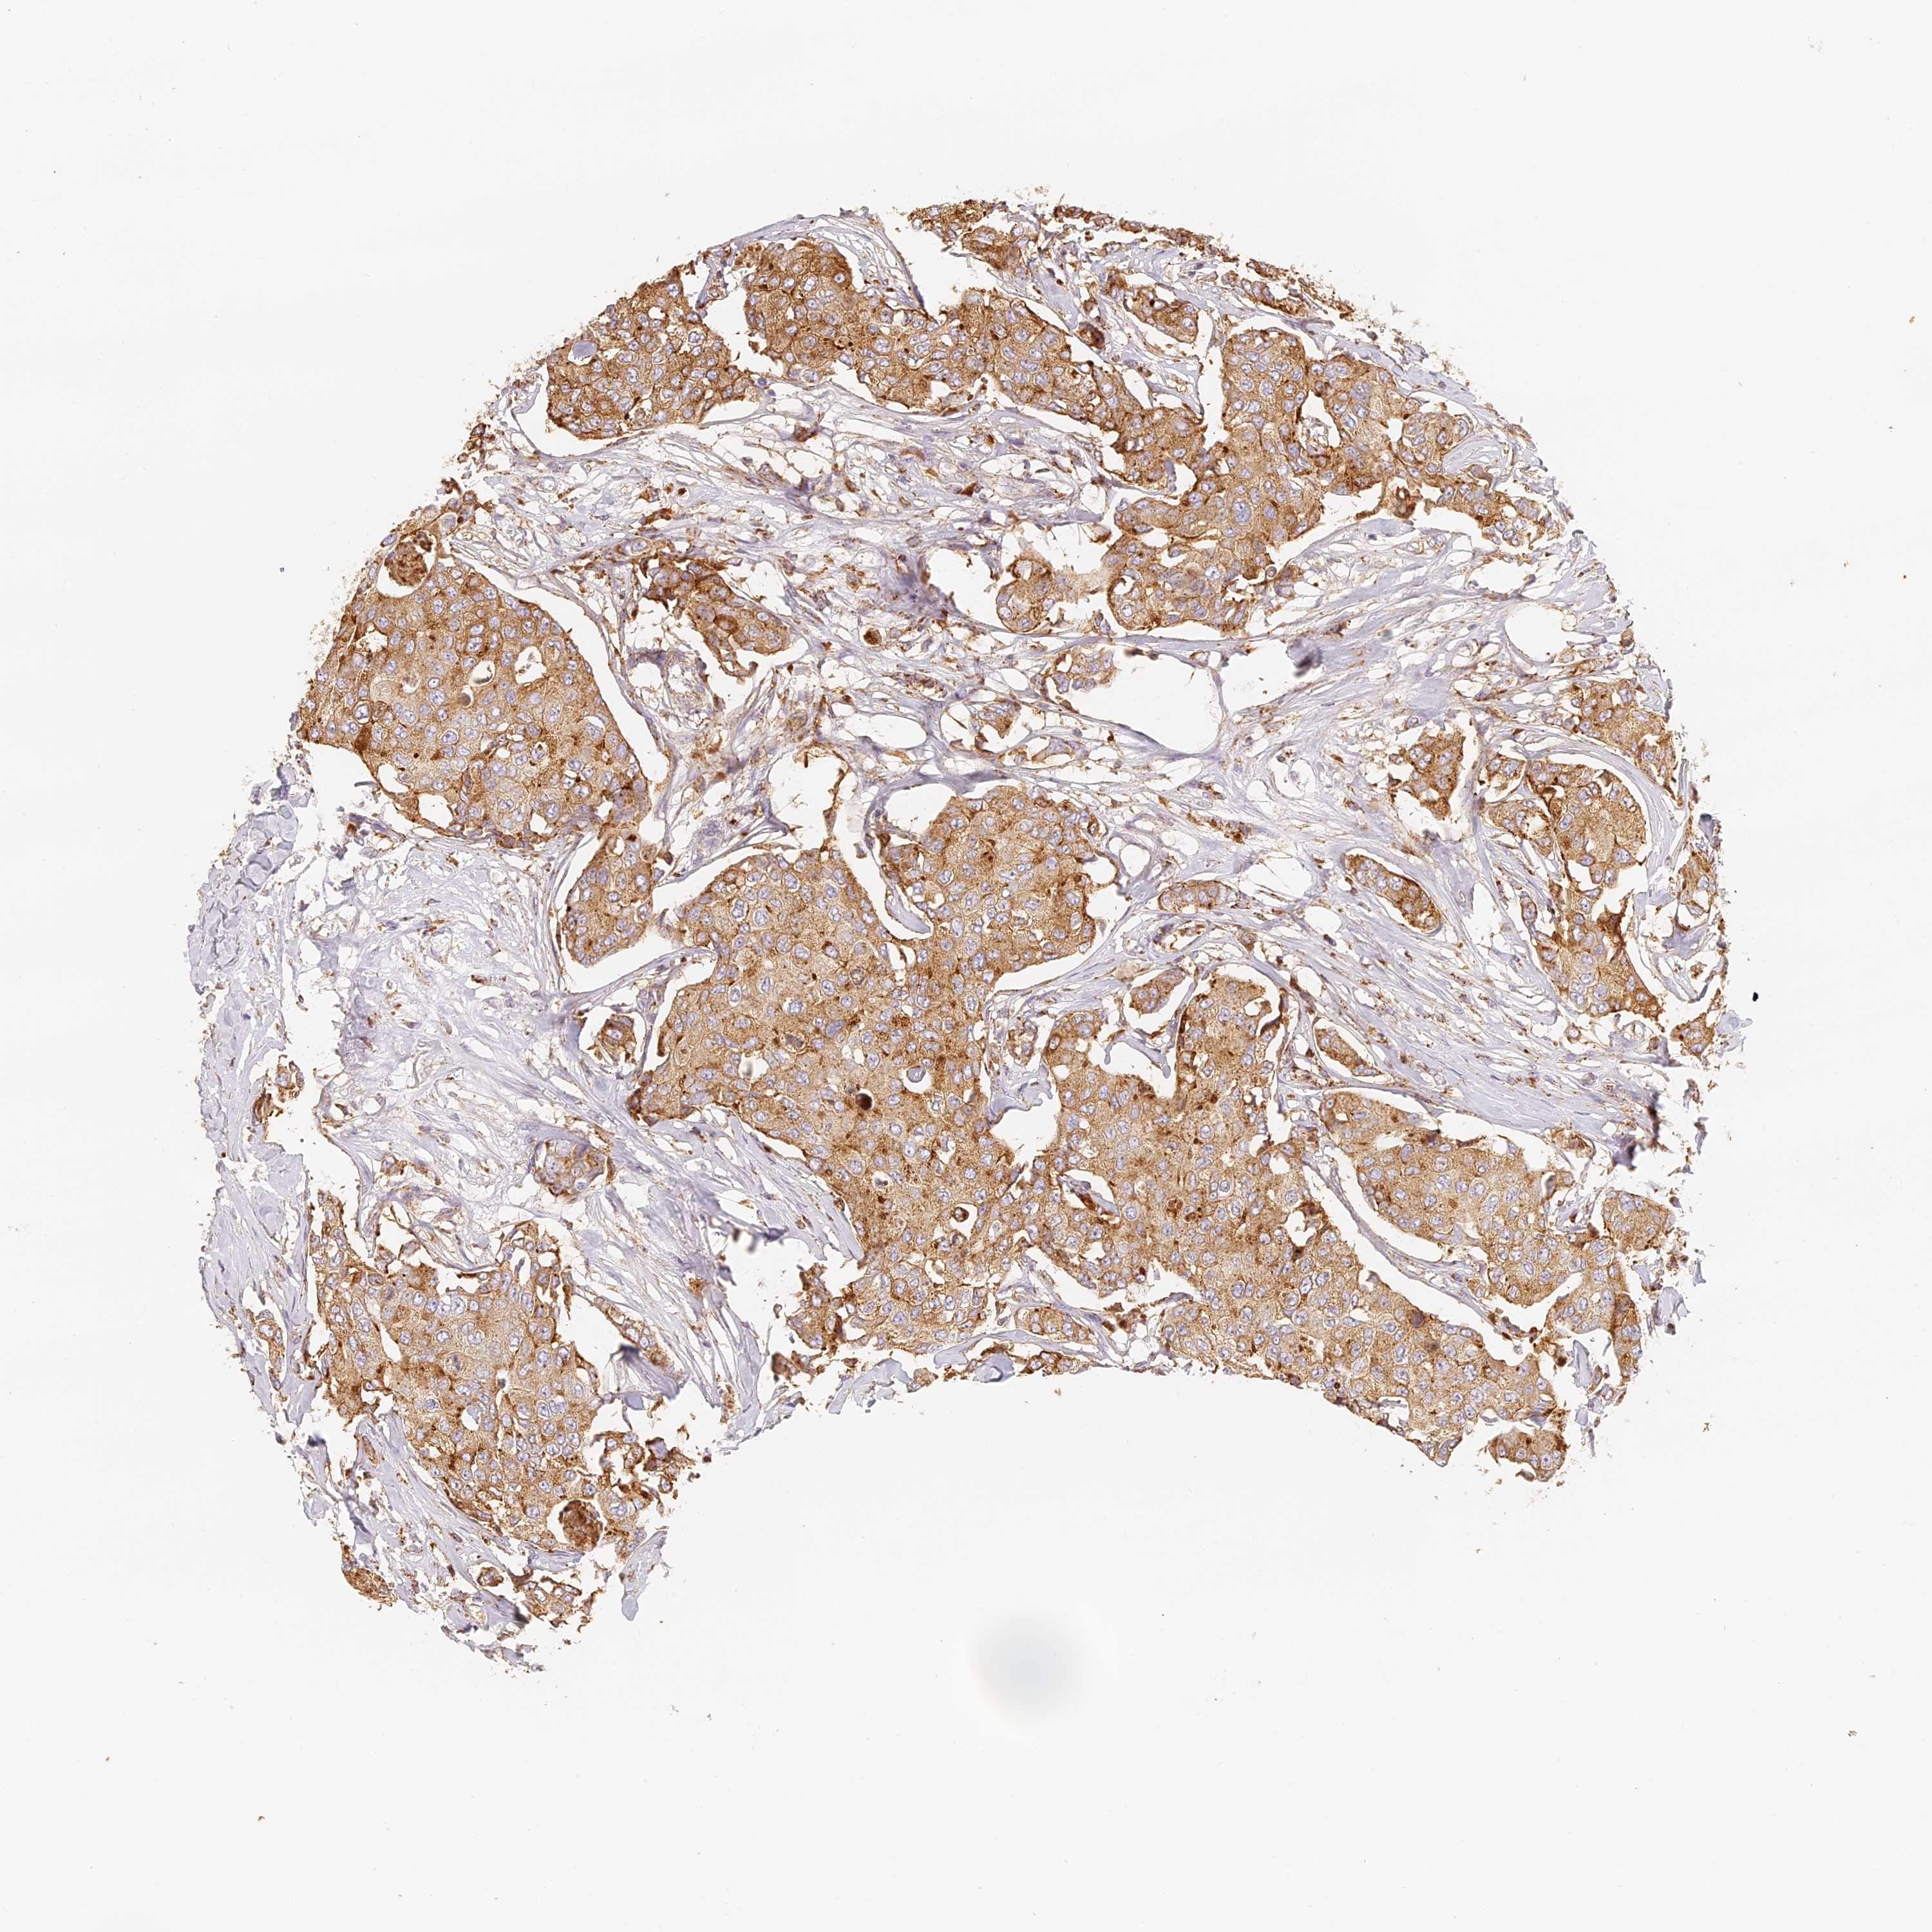

CANCER BREAST CANCER Show tissue menu

BRCA TCGA BRCA VALIDATION PROTEIN EXPRESSION

ANTIBODIES

AND

VALIDATION